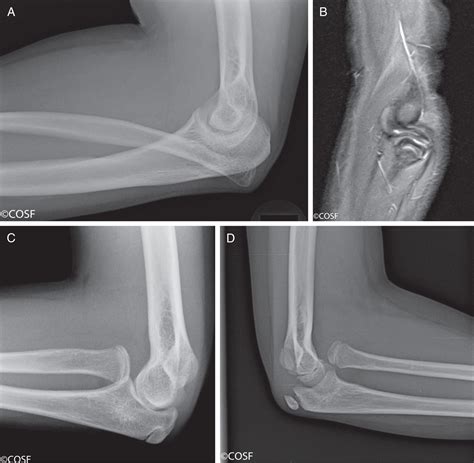

Diagnosing radial head subluxation typically involves a physical examination by a healthcare provider. The diagnosis is usually based on the child's history and the characteristic symptoms. In some cases, an X-ray may be ordered to rule out other potential injuries, such as fractures. However, X-rays are not always necessary for diagnosing radial head subluxation, as the condition is primarily clinical.

If radial head subluxation is suspected, the healthcare provider may perform a specific maneuver to reduce the dislocation. This procedure is typically quick and effective, providing immediate relief to the child.

• radial head subluxation x ray

• radial head subluxation reduction